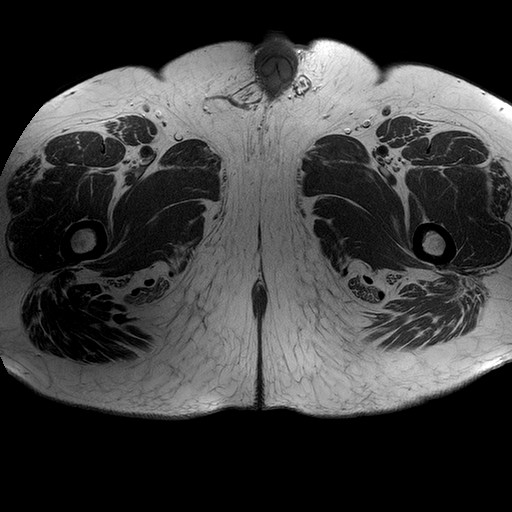

Esami: RMN BACINO

T1W_TSE

Evidenti e simmetriche alterazioni osteofitosiche in regione coxo femorale con riduzione delle rime articolari. Degenerazione completa del cercine glenoideo. Non attuali segni di versamento articolare. Non segni di edema osseo che escludono attuale algodistrofia od osteonecrosi. Lieve e simmetrica riduzione del trofismo della muscolatura glutea.